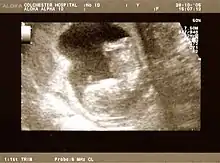

Fetus at 20 weeks

Fetal assessments

Obstetric ultrasonography is routinely used for dating the gestational age of a pregnancy from the size of the fetus, determine the number of fetuses and placentae, evaluate for an ectopic pregnancy and first trimester bleeding, the most accurate dating being in first trimester before the growth of the foetus has been significantly influenced by other factors.[22] Ultrasound is also used for detecting congenital anomalies (or other foetal anomalies) and determining the biophysical profiles (BPP), which are generally easier to detect in the second trimester when the foetal structures are larger and more developed.[23]

X-rays and computerized tomography (CT) are not used, especially in the first trimester, due to the ionizing radiation, which has teratogenic effects on the foetus.[24] No effects of magnetic resonance imaging (MRI) on the foetus have been demonstrated,[25] but this technique is too expensive for routine observation. Instead, obstetric ultrasonography is the imaging method of choice in the first trimester and throughout the pregnancy, because it emits no radiation, is portable, and allows for realtime imaging.[26]

The safety of frequent ultrasound scanning has not been confirmed. Despite this, increasing numbers of women are choosing to have additional scans for no medical purpose, such as gender scans, 3D and 4D scans.[27] A normal gestation would reveal a gestational sac, yolk sac, and fetal pole.[28]

The gestational age can be assessed by evaluating the mean gestational sac diameter (MGD) before week 6, and the crown-rump length after week 6. Multiple gestation is evaluated by the number of placentae and amniotic sacs present.[29]